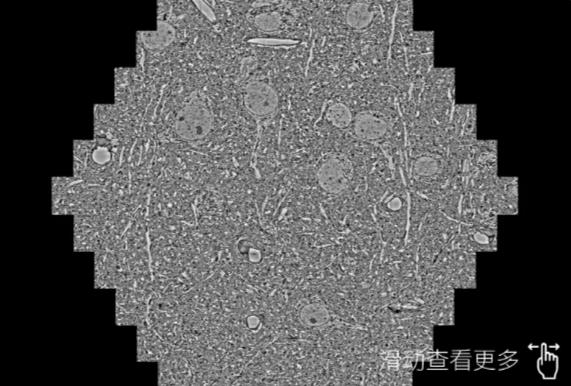

鼠脑切片。左图使用六安蔡司六安扫描电镜MultiSEM706对165μmx143pm面积区域成像,耗时仅需1.5秒。右图为鼠脑切片中30μm区域放大效果。样品由芝加哥大学B.Kasthuri提供。

使用蔡司高速六安扫描电镜MultiSEM对1mm²人脑皮层组织进行高分辨成像,并对其中的各种细胞结构进行三维重构分析。左图展示了2x3mm²组织平面中锥体神经元的三维重构效果。右图显示了局部体积神经元三维重构。图像由哈佛大学chtman实验室提供,渲染图由D. Berger 制作。